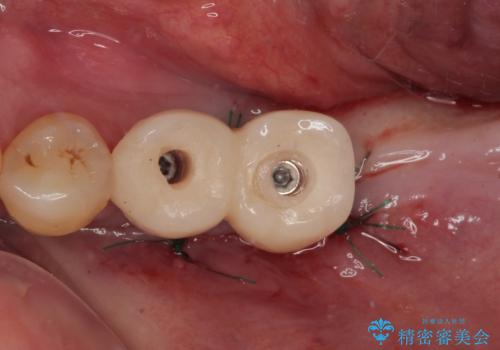

- 連結されている奥歯がグラグラしていて、インプラント治療を希望して来院された患者様です。

連結の手前の歯は歯根が破折して、クラウンが歯から外れており、奥の歯は動揺により歯根周辺の骨が吸収している状態でした。

骨吸収が甚大な後方は3ヶ月ほど待機して、手前は抜歯即時埋入により、短期間インプラント補綴治療を行うこととしました。

なお、後方の歯は痛みが酷かったため、初診時に抜歯をすることとなりました。

骨吸収が大きかったため、待機期間を必要としましたが、外科処置は初診時の抜歯も含めて3回に抑えることができ、半年の短期間で治療を終えることができました。